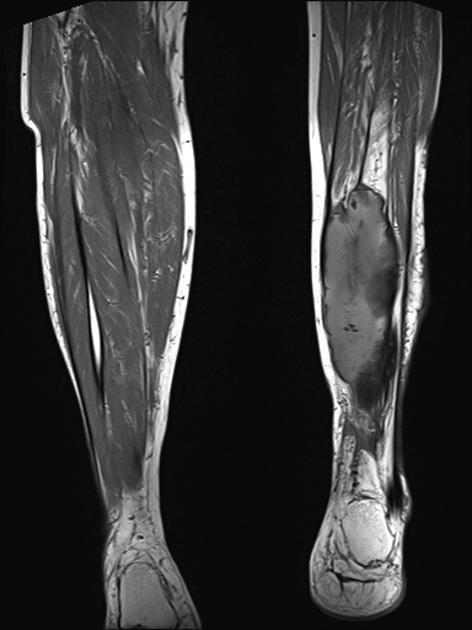

Figure 5 is a T-1 weighted image of an MO lesion in the left lower leg. It is fairly isointense to muscle on this image with a low signal periphery. Figure 6 is an accompanying STIR image, which demonstrates a fatty component and thus manifests a uniformly low signal.

MRI may be used as a means of assessing the extent of the lesion. In the early phase, the lesion is isointense to muscle on the T-1 weighted images and hyperintense to muscle on T-2. As progressive ossification of the periphery occurs in the subacute phase, there will be the formation of a hypointense outer rim on the T-1 weighted images (3). Enhancement is present on the post-contrast images. With further maturation, the lesion becomes hypointense on both the T-1 and T-2 weighted sequences.